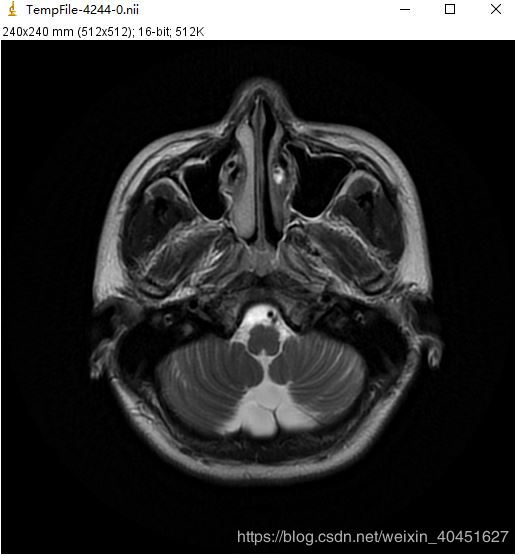

同一张Dicom文件使用sitk.Show()得到的效果如下图:

除此之外,ImageJ还有一个Tool Bar 支持对图像的进一步处理:

可见,SimpleITK的可视化要比上面介绍的强大很多,不仅可以实现单张图像的可视化以及图像处理,还可以同时对整个序列的图像进行统一处理.